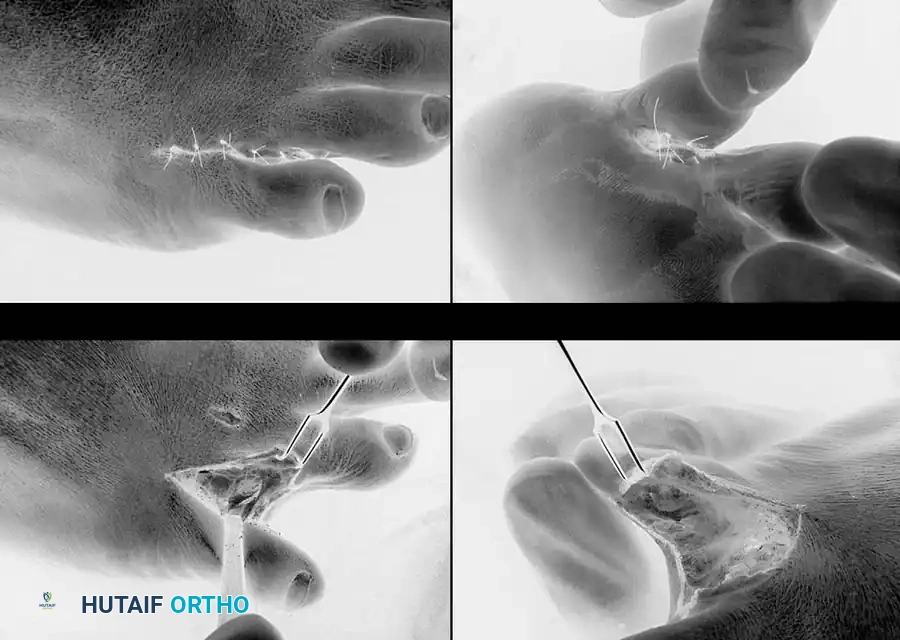

🔪 Surgical Technique 80-9: Bony Resection and Partial Syndactylization

A web space corn is highly prone to recurrence if adequate bone is not removed. Resecting the lateral flare of the base of the proximal phalanx of the fourth toe flush with the diaphysis, or removing the head and neck of the proximal phalanx of the fifth toe, may be curative. Occasionally, both must be resected. For recurrent or intractable interdigital corns, a partial, simple syndactylization is highly effective.

• Incision Design: Make a dorsal longitudinal incision extending into the plantar portion of the interdigital space. Extend the two limbs into the adjacent sides of the plantar third of the opposing toes. Placing the digital limbs of the incision on the adjacent plantar sides retains the cosmetic cleft the patient sees from the dorsal aspect.

• Bone Resection (Fourth Toe): If the center of the hyperkeratotic area is more on the fourth phalangeal side, resect the lateral flare of the base of the proximal phalanx of the fourth toe flush with the diaphysis (Fig. 80-26A).

• Bone Resection (Fifth Toe): If the lesion is more on the fifth toe side, resect the medial portion of the head of the proximal phalanx of the fifth toe (Fig. 80-26B). This can be done through a dorsal transverse elliptical incision or a dorsolateral curved incision.

• Palpation: Palpate the web space after resection to determine if any residual bony impingement exists. If the resection seems inadequate, the opposite bony offender must be resected.

• Syndactylization Closure: Close the wound beginning proximally and extending distally, suturing the dorsal limbs together (Fig. 80-26C). Excise a small amount of skin at the apex of the dorsal skin